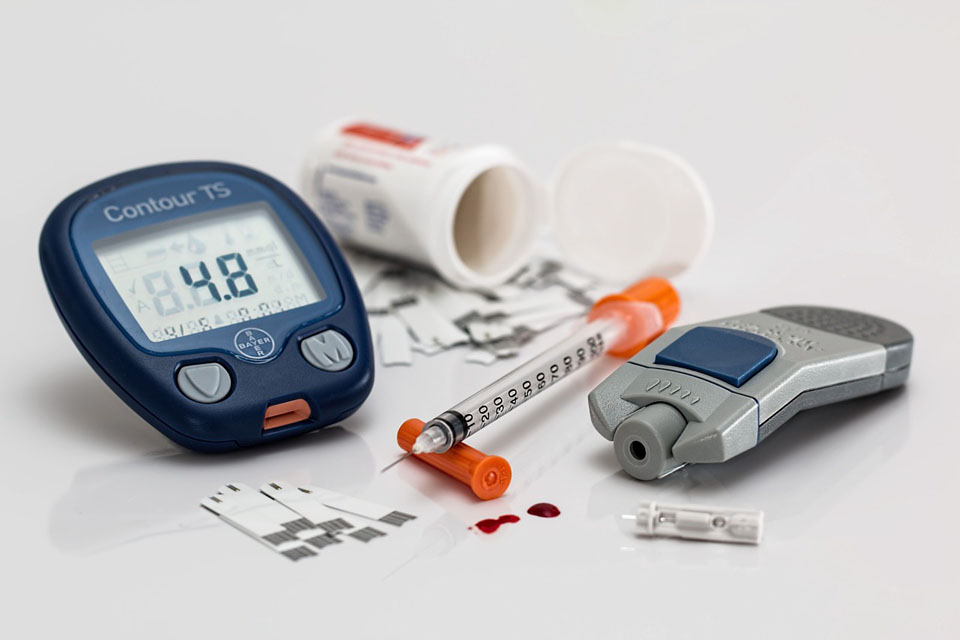

A fogágybetegséget súlyosbító legfontosabb tényező a cukorbetegség. Amennyiben nem kezelik megfelelően, ennek a betegségnek súlyos csontpusztulás és fogvesztés lehet a következménye. Ez még akkor is igaz, ha a páciens szájhigiéniája egyébként kiváló, és semmilyen más rizikófaktor nincs jelen.

A kezeletlen cukorbetegség azért ilyen veszélyes, mert a betegség közben kialakuló tartós változások megakadályozzák, hogy az immunrendszer megfelelő választ adjon a kórokozók támadására. Minden egyéb immunválaszt gátló tényező (például HIV-fertőzés; súlyos, hosszan tartó betegségek következtében, illetve gyógyszerszedés miatt kialakult immunhiányos állapot) hasonló hatással lehet a fogat körülvevő szövetekre.